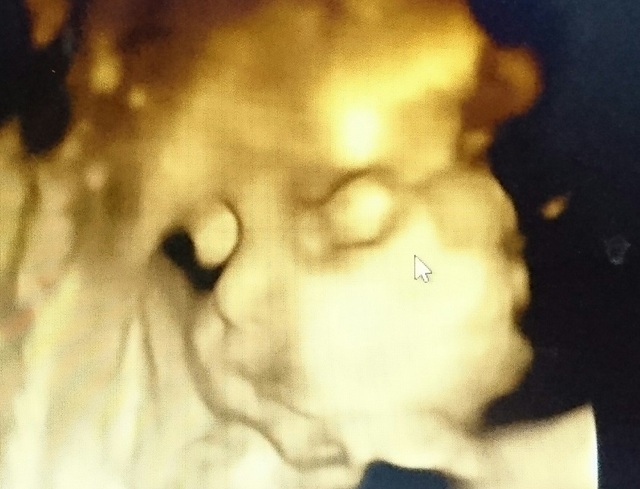

29週0日(29w0d・女の子)|みちゃこ88 さん(28歳)

エコー写真撮影時のエピソード:

初めて顔がはっきり見えました!小さいと言われてて心配だったけど、ぷっくりしてきて安心しました。

でも膀胱炎になってしまってたくさん水分を取るようになったのでトイレが近くて夜何回も起きてしまいます( ; _ ; )がんばって乗り越えよう!